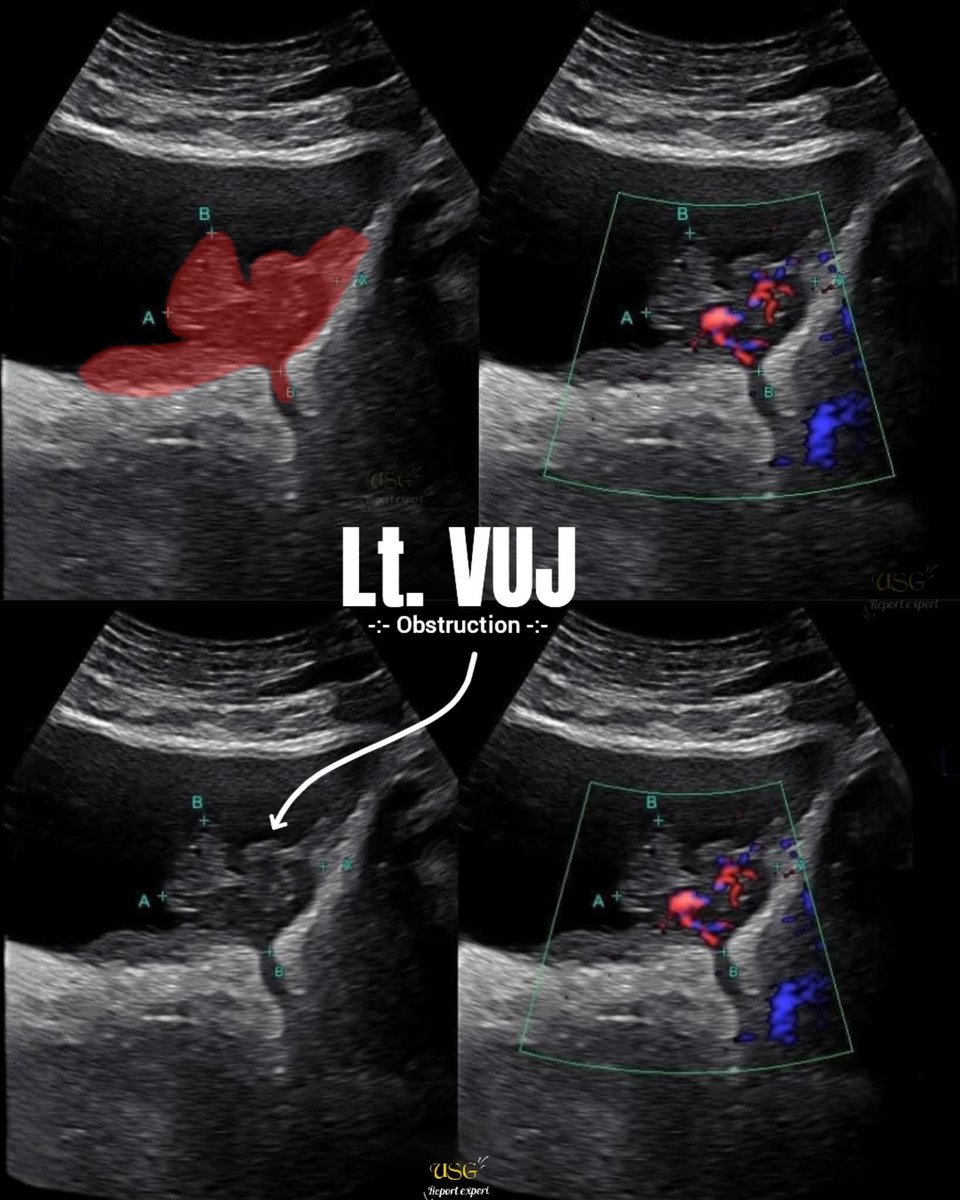

History of burning michuration and Hematuria 🩸 for 3 months || Left side moderate hydronephrosis noted 😲😲

#ultrasound #sonography #radiology #medicalimaging #ultrasoundlearning #medicaleducation #healthcare #performance #TeamSpirit